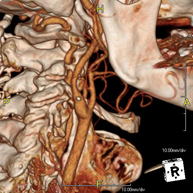

- Angio – TC Troncos Supraaórticos Prueba radiológica que consiste en obtener imágenes de las arterias carótidas del cuello de alta definición anatómica mediante el empleo de un equipo de TC (Tomografía Computarizada) y la inyección de contraste intravenoso. Posteriormente, las imágenes son reconstruidas en tres dimensiones (3D). Indicaciones: accidente vascular cerebral agudo, accidente vascular transitorio, soplo carotídeo. Prueba radiológica que consiste en obtener imágenes de las arterias carótidas del cuello de alta definición anatómica mediante el empleo de un equipo de TC (Tomografía Computarizada) y la inyección de contraste intravenoso. Posteriormente, las imágenes son reconstruidas en tres dimensiones (3D). Indicaciones: accidente vascular cerebral agudo, accidente vascular transitorio, soplo carotídeo.